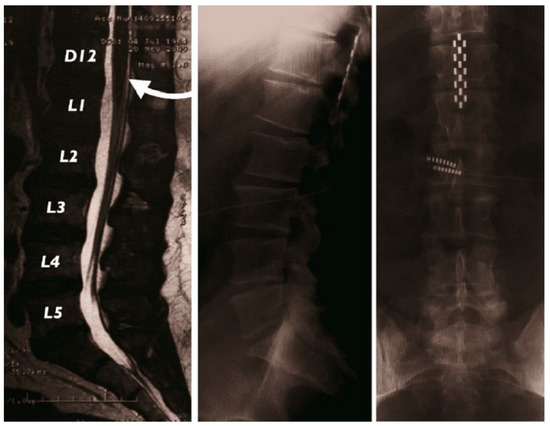

2.1.2. Surgical Implantation

2.1.3. Electrostimulation Mapping of the Conus Medullaris